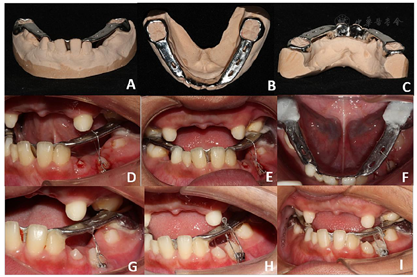

治疗过程:①局麻下,分四次拔除滞留乳牙;②2021年5月6日,局麻下行左下前磨牙区外科开窗手术,去除33、34、35冠方阻力,联合下颌固定矫治器正畸牵引34;(图10)③2021年8月19日,局麻下行上颌前牙区多生牙拔除术(3枚)(图11);④2021年9月12日,佩戴螺旋快速扩弓器扩大上颌牙弓。